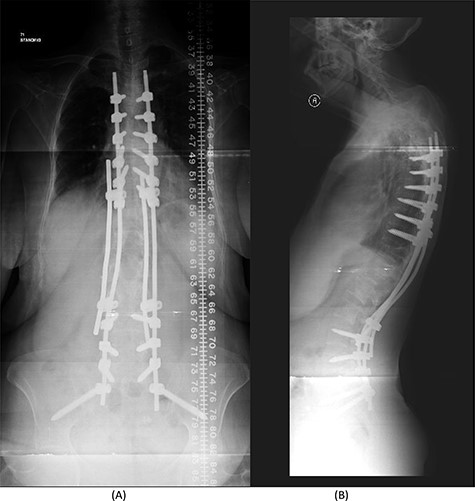

(A) AP lumbar spine X-ray demonstrating the bridging technique. (B) Lateral spine X-ray showing the bridging technique sparing the infected area.

The bridging technique was used to achieve relative stability through posterior fixation until the anti-TB medications cleared the vertebral infection and allowed re-ossification of the destructed levels (T11–L3) to occur. An open biopsy was done intraoperatively to reconfirm the diagnosis of spinal TB. The patient started mobilizing early postoperatively and continued to take the anti-TB medications for 18 months (Fig. 4).

The success rate of surgical TB management is high and effective according to a study based on data collected from 582 patients throughout 11 years [8]. Our patient presented with a destructive spinal lesion and underwent posterior spinal decompression and instrumentation of T11–L3. Nevertheless, due to severe destruction, loosening and poor bone quality of the levels T11–L3, along with the multiple medical comorbidities, anterior surgical intervention with a thoracoabdominal approach with resection of all the levels involved would associate with major morbidities and complications. To achieve a balanced construct and to have multiple fixation points, which was needed to overcome the poor bone quality, the fixation was done from T5 down to the pelvis (Fig. 4), spanning the destructed area and utilizing the bridging technique with multiple rod constructs across the T11–L3 region.